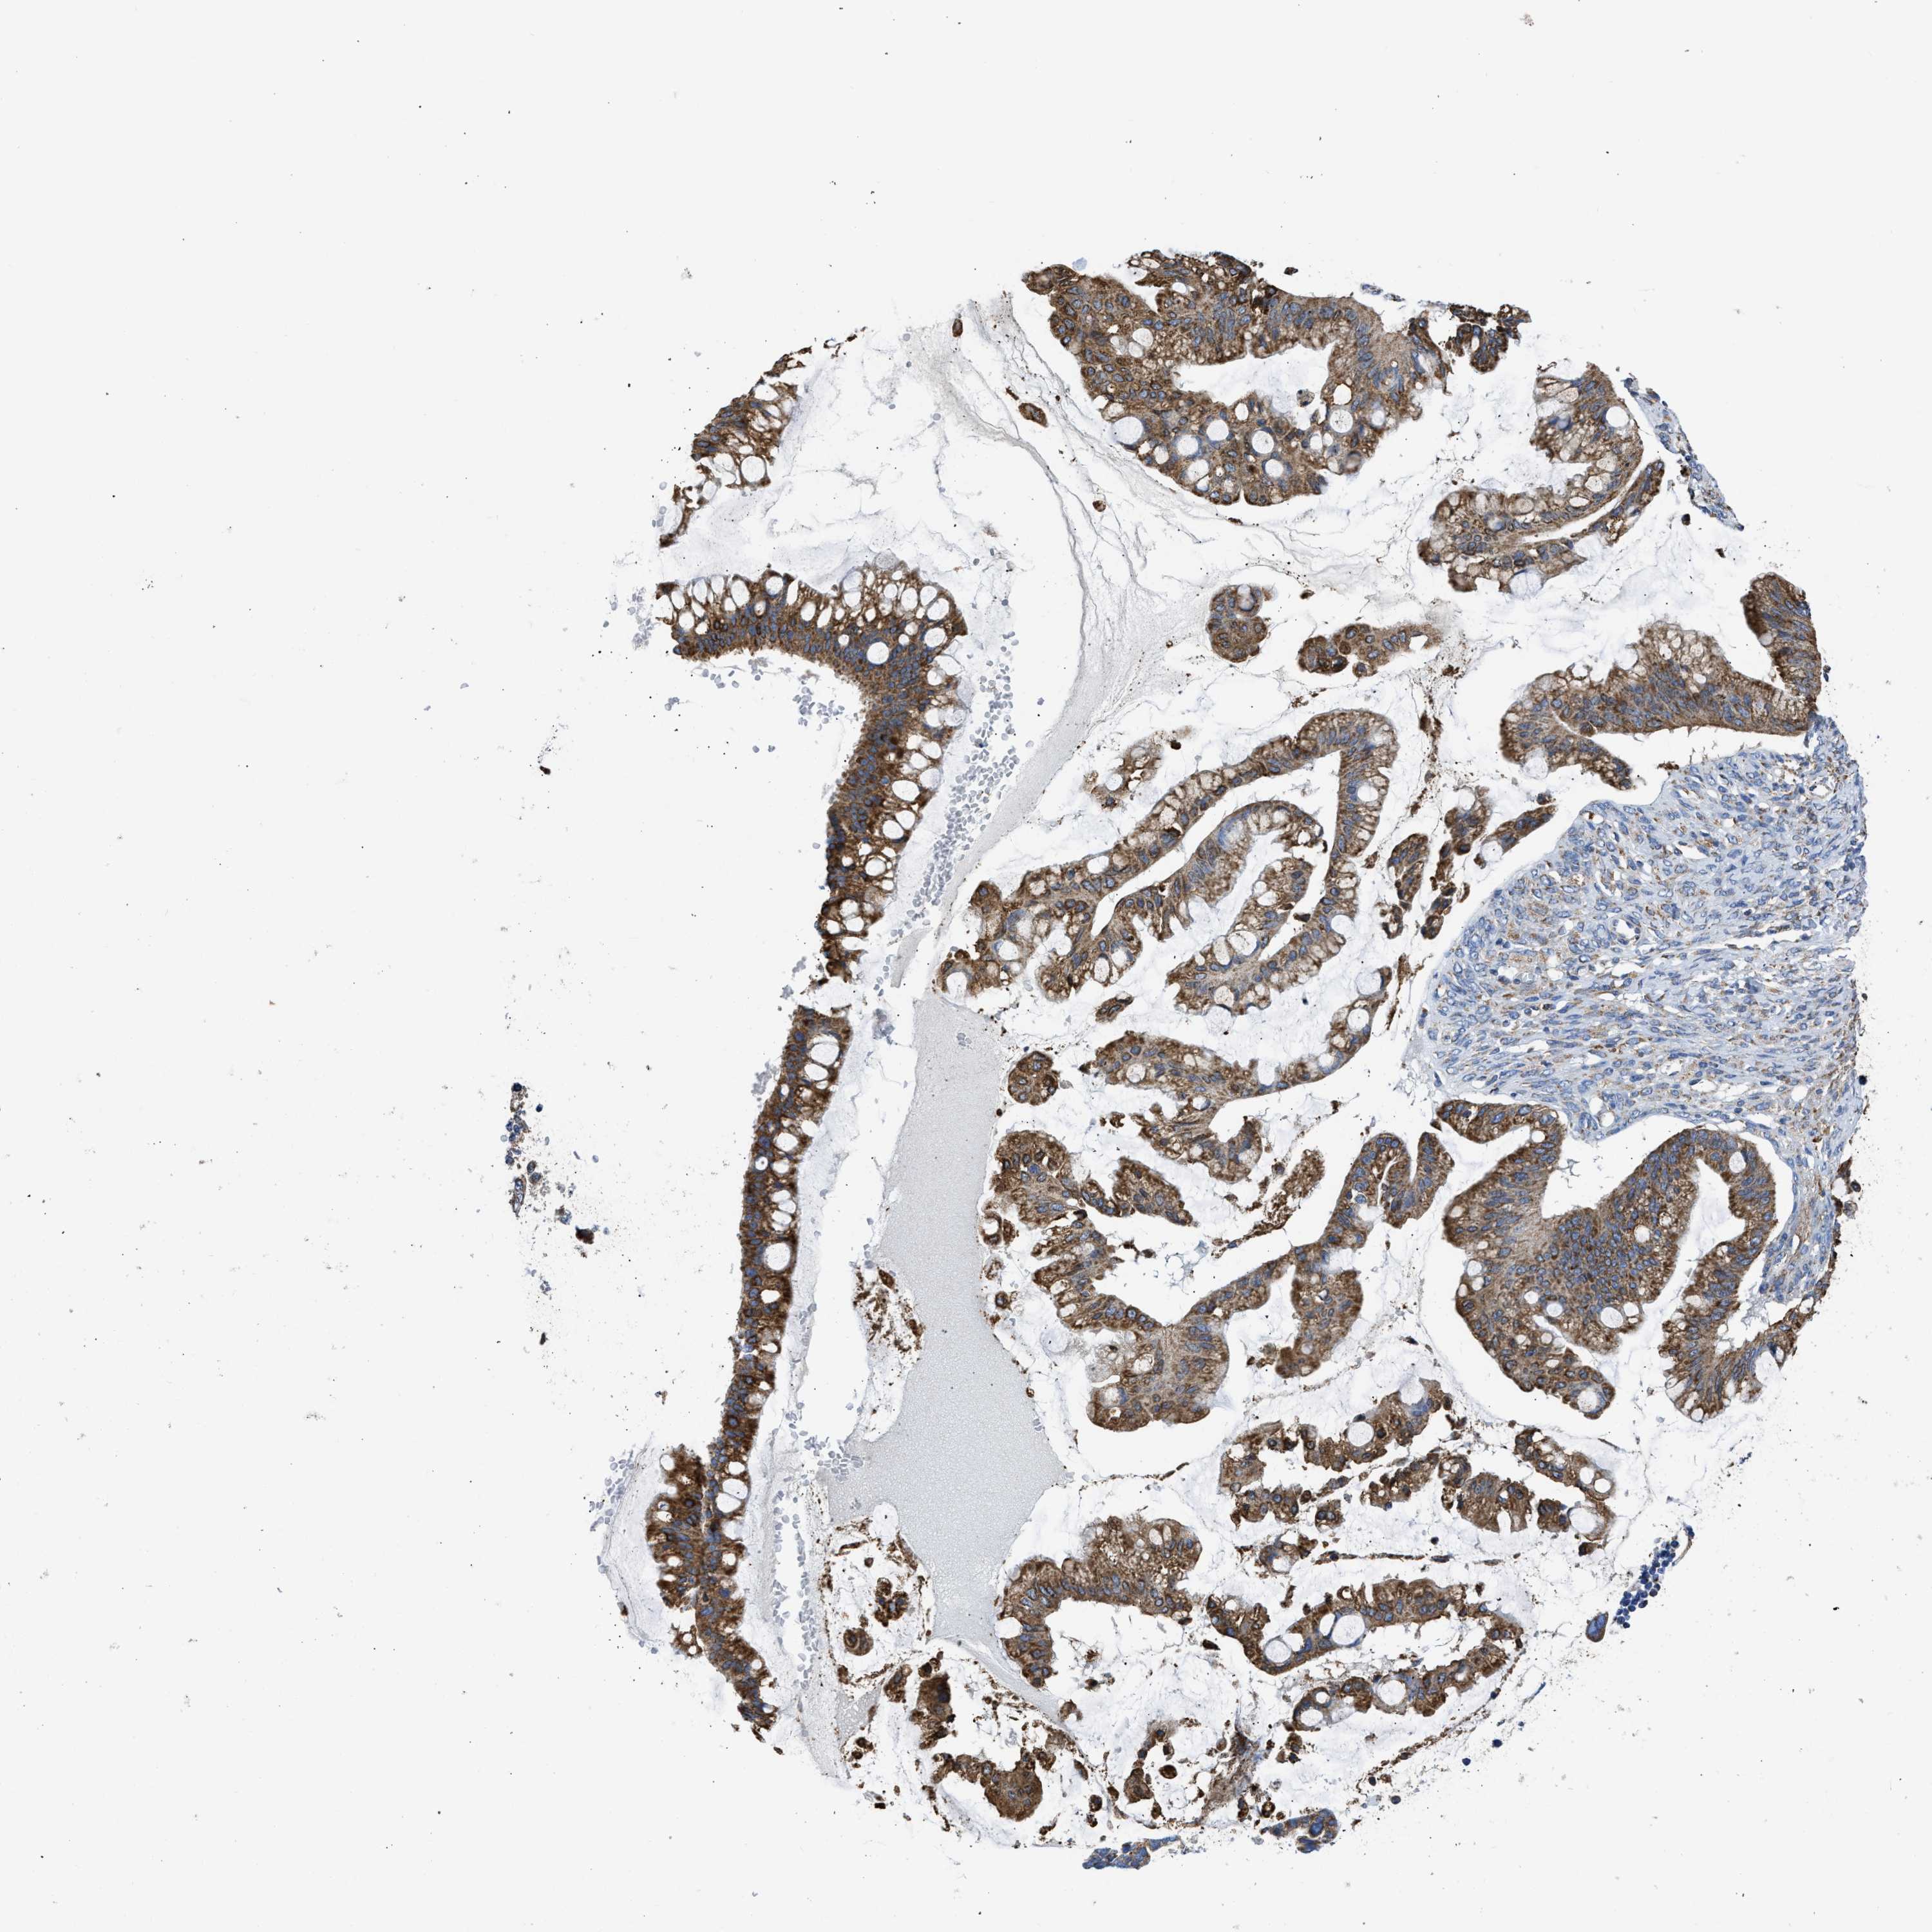

OVARIAN CANCER - Protein expressioni

A mouse-over function shows sample information and annotation data. Click on an image to view it in a full screen mode. Samples can be filtered based on level of antibody staining by selecting one or several of the following categories: high, medium, low and not detected. The assay and annotation is described here.

Note that samples used for immunohistochemistry by the Human Protein Atlas do not correspond to samples in the TCGA dataset.

Antibody stainingi

Antibody staining in the annotated cell types in the current human tissue is reported as not detected, low, medium, or high, based on conventional immunohistochemistry profiling in selected tissues. This score is based on the combination of the staining intensity and fraction of stained cells.

Each image is clickable and will lead to virtual microscopy that enables deeper exploration of all samples and also displays staining intensity scores, fraction scores and subcellular localization as well as patient and tissue information for each sample.

Antibody CAB004222

Cystadenocarcinoma, serous, NOS

Cystadenocarcinoma, mucinous, NOS

Carcinoma, endometroid

Carcinoma, NOS